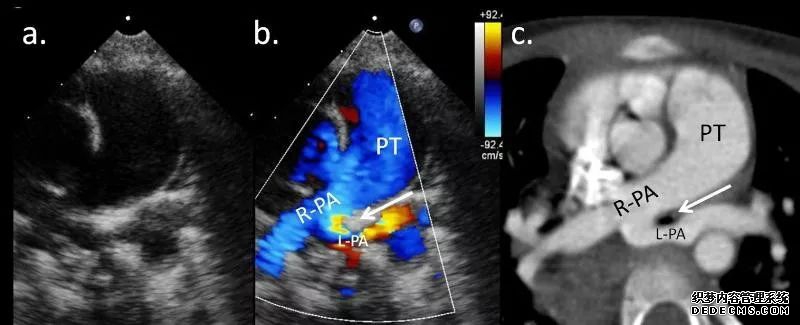

4、心脏超声: 能较好明确心内畸形及异常起源的左肺动脉,但对于显示心外肺动脉走行情况及异常发育的气管,超声无法观察,另外也与操作者的技能有关;

(超声及 CT)